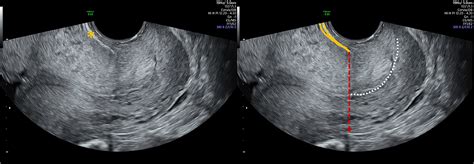

The cervix is the lower part of the uterus that connects to the vagina. During pregnancy, the cervix plays a vital role in keeping the baby secure within the uterus. Cervical length refers to the measurement of the cervix from the internal os (the opening to the uterus) to the external os (the opening to the vagina). This measurement is typically taken using transvaginal ultrasound, which provides a clear view of the cervix.

• Transvaginal Ultrasound: This is the most common method for measuring cervical length. It provides a clear view of the cervix and is generally performed between 18 and 24 weeks of gestation.

• Diagnosis: Cervical insufficiency is typically diagnosed through transvaginal ultrasound, which measures cervical length and assesses cervical function.